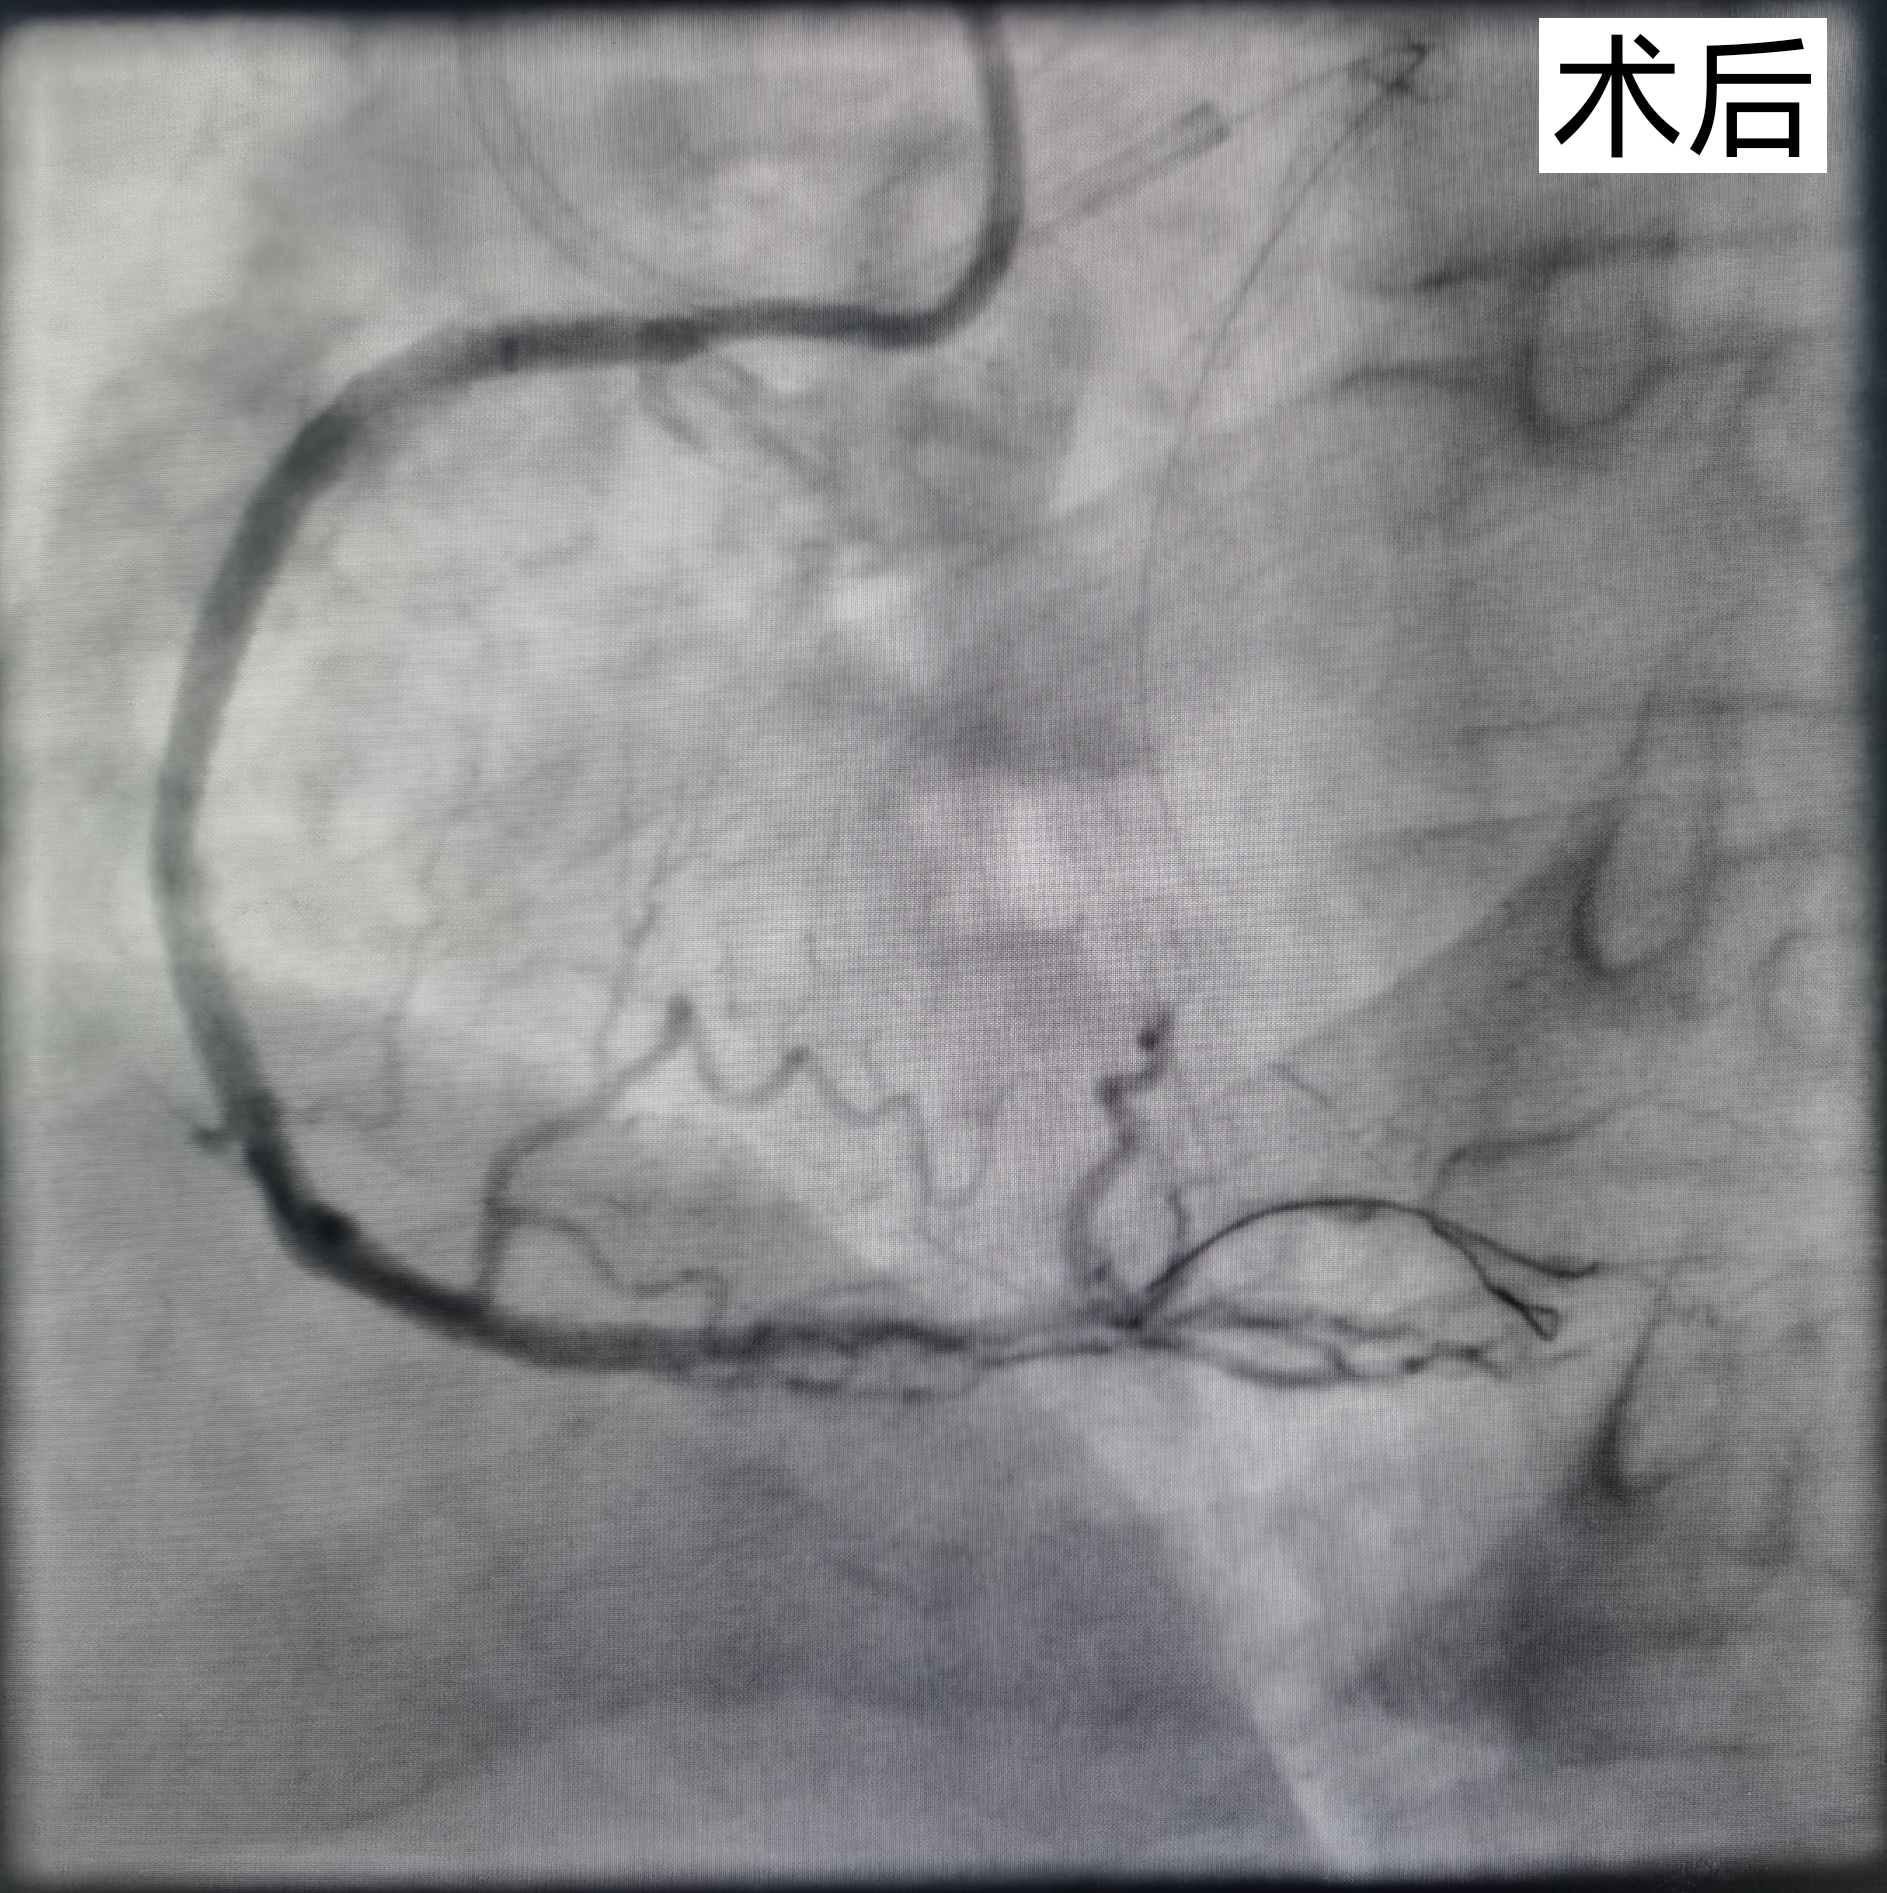

术后血流通畅。

8月18日,范先生接受第二次手术,准备开通完全闭塞的右冠脉血管,该血管共有三处闭塞,并且有明显钙化。手术进行了7个小时,潘宏伟主任带领团队克服一次次的艰难险阻,不断尝试,终于成功开通血管,植入支架。